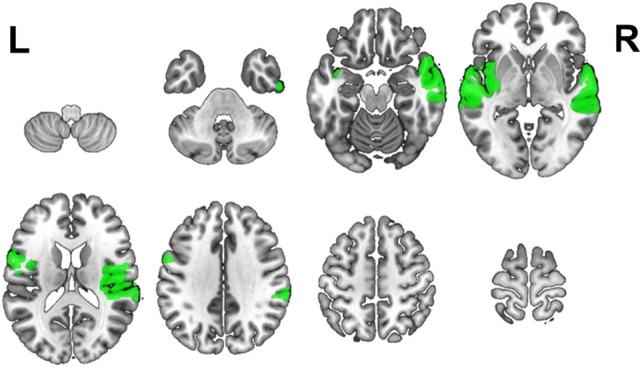

Language comprehension is a complex process involving an extensive brain network. Brain regions responsible for prosodic processing have been studied in adults; however, much less is known about the neural bases of prosodic processing in children. Using magnetoencephalography (MEG), we mapped regions supporting speech envelope tracking (a marker of prosodic processing) in 80 typically developing children, ages 4-18 years, completing a stories listening paradigm. Neuromagnetic signals coherent with the speech envelope were localized using dynamic imaging of coherent sources (DICS). Across the group, we observed coherence in bilateral perisylvian cortex. We observed age-related increases in coherence to the speech envelope in the right superior temporal gyrus (r = 0.31, df = 78, p = 0.0047) and primary auditory cortex (r = 0.27, df = 78, p = 0.016); age-related decreases in coherence to the speech envelope were observed in the left superior temporal gyrus (r = - 0.25, df = 78, p = 0.026). This pattern may indicate a refinement of the networks responsible for prosodic processing during development, where language areas in the right hemisphere become increasingly specialized for prosodic processing. Altogether, these results reveal a distinct neurodevelopmental trajectory for the processing of prosodic cues, highlighting the presence of supportive language functions in the right hemisphere. Findings from this dataset of typically developing children may serve as a potential reference timeline for assessing children with neurodevelopmental hearing and speech disorders.

语言理解是一个涉及广泛脑网络的复杂过程。已有研究探讨了负责韵律处理的大脑区域,但对于儿童韵律处理的神经基础知之甚少。本研究使用脑磁图(MEG),在 80 名年龄在 4 至 18 岁之间、完成故事聆听范式的典型发育儿童中,定位了支持语音包络跟踪(韵律处理的标志)的脑区。使用相干源动态成像(DICS)定位与语音包络相干的神经磁信号。在整个组中,我们观察到双侧颞旁皮层的相干性。我们观察到右颞上回(r=0.31,df=78,p=0.0047)和初级听觉皮层(r=0.27,df=78,p=0.016)与语音包络相干性随年龄增长而增加;左颞上回(r=-0.25,df=78,p=0.026)与语音包络相干性随年龄增长而降低。这种模式可能表明,在发育过程中,负责韵律处理的网络得到了进一步的细化,其中右半球的语言区域越来越专门用于韵律处理。总之,这些结果揭示了韵律线索处理的独特神经发育轨迹,突出了右半球支持语言功能的存在。本典型发育儿童数据集的研究结果可能成为评估神经发育性听力和言语障碍儿童的潜在参考时间线。